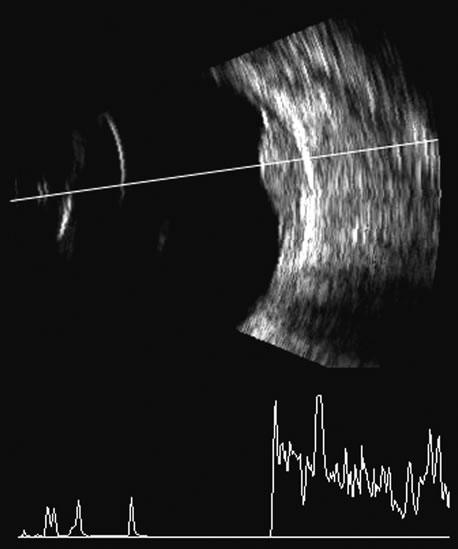

Malignant melanoma varies in its ultrasound presentation from a relatively homogeneous to heterogenous lesion on B-scan. The typical uveal melanoma absorbs sound so that the posterior section is relatively less echoic than the anterior aspect, producing a gradually decreasing amplitude, often to baseline on the A-scan (Fig. 21).

Melanomas also have varying amounts of melanin, a highly acoustically reflective pigment. As noted, melanomas characteristically show high reflectivity anteriorly, with decreasing reflectance as the sound traverses the tissue. This produces the decreasing amplitude posteriorly in the tumor seen on A-scan and gray-scale B-scan. This effect often enhances the anterior scleral boundary. The posterior tumor border is thus measured as the first “rising” echo from the tumor decline, and it is most easily seen and accurately identified on B-scan.27

Fig. 22. Some hemangiomas and metastatic carcinomas may simulate a melanoma. They are differentiated on the basis of a very high amplitude internal echo complex for the hemangioma, a moderately low but sustained echo pattern for the metastasis, and an A-scan with decreasing reflectance as the tumor thickness is traversed. In the center scan of a melanoma, note the double anterior layer caused by edema fluid underlying the crest of the melanoma (arrow).